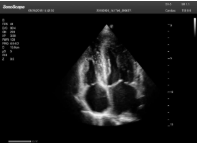

2相控陣探頭

探頭面是平面,接觸面小,近場視野最小,遠(yuǎn)場視野大,成像視野呈扇形,適用于心臟。

心臟探頭通常按應(yīng)用人群劃分為成人、兒童、新生兒三類:(1)成人心臟位置最深、搏動速度慢;(2)新生兒心臟位置較淺、搏動速度最快;(3)兒童心臟的情況介于新生兒與成人之間。

肥厚性心肌病-心尖四腔